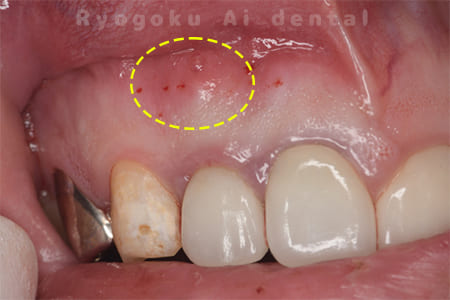

前歯の腫れが治らない、とのことでご来院された患者様です。前歯には他院で自費で入れた被せ物が入っており、被せ物のやり変えと共に根管治療の提案を致しましたが、このままの状態での治療を希望されたため、歯根端切除術を行いました。手術後の痕も気にならずに、腫れもなくなり、非常に満足して頂きました。半年経過を追っておりますが、現在も再発等ございません。

<リスク・副作用>

外科手術のため、術後に出血、痛みや腫れ、違和感を伴います。口腔内の状態によっては適応できないことがあります。歯根端切除で治らなければ抜歯を検討しなくていけない場合もあります。